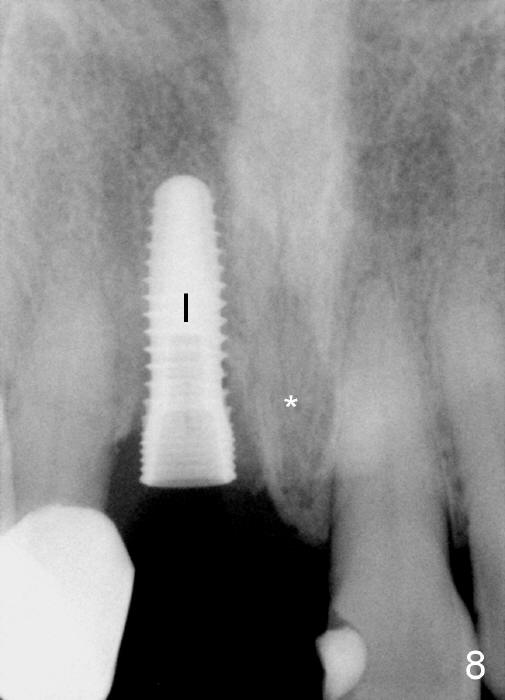

A 64-year-old lady requests replacing #7 and 8 crowns (Fig.1,2). When #8 is extracted, the labial plate is found to be missing (Fig.3). Following 2 mm pilot drill (Fig.4,5 P), 3.8 mm tap drill (Fig.6,7 T) and 4.5x14 mm implant (Fig.8 I) and 4.8 mm abutment (Fig.9 A), corticocancellous bone is harvested from the left tuberosity and placed in the labial gap of the socket (Fig.10 G). Collagen dressing is placed over the bone graft (Fig.11 C). The former is secured in place by an immediate provisional (P).

Four-month follow up shows that bone graft from the tuberosity appears to have healed with the implant microthreads (Fig.17 *); there is a diastema between #8 and 9 (arrowheads). Before removal of the provisionals of #7 and 8 for final impression, new composite is added to the mesial surface of #9 as the first step of closure of the diastema (Fig.18 <).